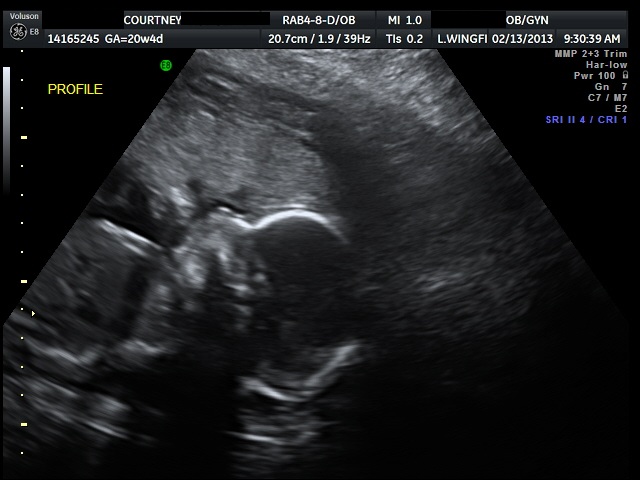

ULTRASOUND_6 February 16, 2013 by Courtney Leave a comment ← Previous Image Next Image → 20w4d Like Loading...